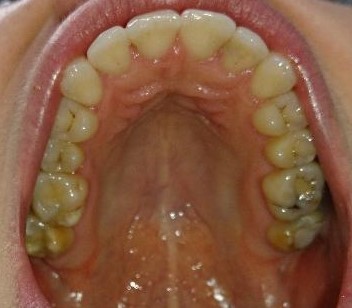

Pacient, 26 ani. Caz nonextracționist, Expander Maxilar + aparate ortodontice fixe bimaxilare.